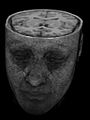

Aus den CT-Einzelschichten zusammengesetztes 3D-Bild

Jedes Pixel in einem Schnittbild entspricht einem Volumenelement (Voxel) des gesamten dreidimensionalen Datensatzes. Die Höhe des Voxels entspricht dabei der Schichtdicke. In der Nachbearbeitung lassen sich aus den Voxeln beispielsweise beliebig im Raum angeordnete Schichtbilder (multiplanare Rekonstruktion, MPR), geschichtete (Subvolumen-)Maximumintensitätsprojektionen (MIPs) oder dreidimensionale Bilder des untersuchten Objekts (Volumenrendering) errechnen.

3D-Rekonstruktion (Volumenrendering) eines MRT-Datensatzes